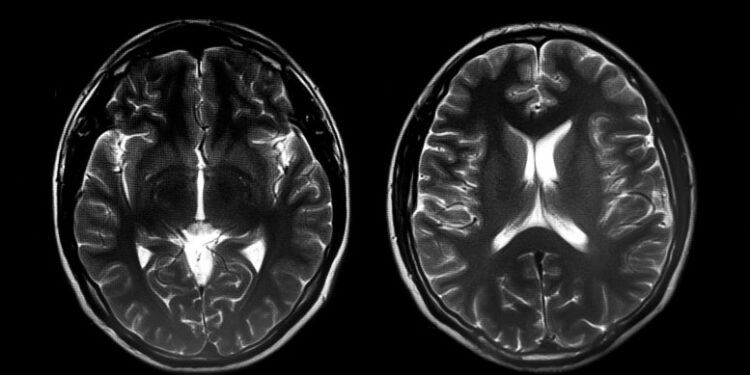

حللت الدراسة فحوصات التصوير بالرنين المغناطيسي الوظيفي للدماغ لـ 773 طفلاً مصابًا بالتوحد – 637 فتى و 136 فتاة. قالت سوبكار إن جمع بيانات كافية لإدراج عدد كبير من الفتيات في الدراسة كان أمرًا صعبًا ، مشيرًا إلى أن العدد القليل من الفتيات المشمولات تاريخيًا في أبحاث التوحد كان عائقًا أمام معرفة المزيد عنهن. اعتمد فريق البحث على البيانات التي تم جمعها في ستانفورد وعلى قواعد البيانات العامة التي تحتوي على مسح للدماغ من مواقع البحث حول العالم.

باستخدام 678 من عمليات مسح الدماغ للأطفال المصابين بالتوحد ، طور الباحثون خوارزمية يمكنها التمييز بين الأولاد والبنات بدقة 86٪ . عندما تحققوا من الخوارزمية في عمليات مسح الدماغ الـ 95 المتبقية للأطفال المصابين بالتوحد ، حافظت على نفس الدقة في التمييز بين الأولاد والبنات.

اختبر العلماء أيضًا الخوارزمية على 976 مسحًا دماغيًا من الأولاد والبنات الذين يتطورون عادةً. لم تتمكن الخوارزمية من التمييز بينهم ، مما يؤكد أن الفروق بين الجنسين التي وجدها العلماء كانت فريدة من نوعها لمرض التوحد.

من بين الأطفال المصابين بالتوحد ، كان لدى الفتيات أنماط اتصال مختلفة عن تلك الموجودة في العديد من مراكز الدماغ ، بما في ذلك أنظمة الانتباه الحركية واللغوية والمكانية. كانت الاختلافات في مجموعة من المناطق الحركية – بما في ذلك القشرة الحركية الأولية ، ومنطقة المحرك التكميلية ، والقشرة الجدارية والجانبية ، والتلف الصدغي الصدغي الأوسط والعليا – هي الأكبر بين الجنسين. بين الفتيات المصابات بالتوحد ، ارتبطت الاختلافات في المراكز الحركية بشدة الأعراض الحركية ، مما يعني أن الفتيات اللواتي كانت أنماط دماغهن أكثر تشابهًا مع الأولاد المصابين بالتوحد يميلون إلى ظهور الأعراض الحركية الأكثر وضوحًا.